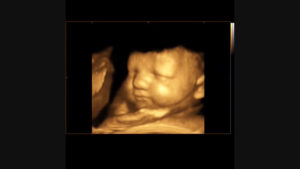

3Д УЗИ делается при беременности с целью детального просмотра частей тела, черт лица плода. При исследовании на экран ультразвукового устройства передается объемное голографическое изображение.

Трехмерное сканирование плода при беременности дает возможность в объемном виде оценить состояние ребенка. Картинка передается на экран аппарата в цветном режиме. Чаще метод используют на втором плановом скрининге, когда четко видны части тела плода.

С помощью 3Д УЗИ делают фотографии и видеозапись движений ребенка в утробе матери. В редких случаях просмотреть малыша не удается из-за того, что он поворачивается спиной. Тогда диагностика проводится через 15–20 минут.

Трехмерное изображение представляется в 3 измерениях — глубине, высоте и ширине. Беременная может увидеть ребенка на экране УЗИ-аппарата в цвете. При этом детально просматривается каждая часть лица и тела, мимика плода.

У него неплохо выражены черты лица. Проводимое 3D-УЗИ в 25 недель позволит увидеть то, как будет выглядеть маленький человек, когда родится. Глаза еще закрыты, брови только начали развиваться, рот сформировался. Продолжает развиваться ушная раковина.